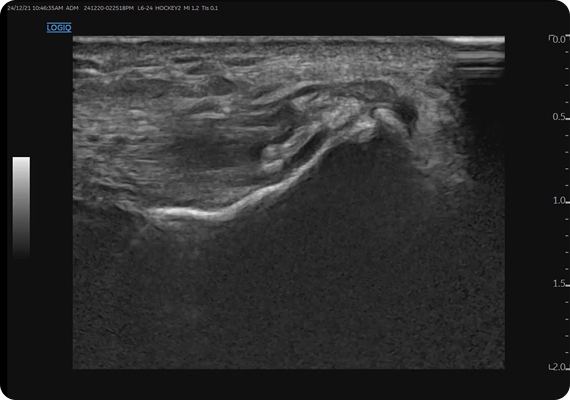

초음파 유도하 침도 요법은 섬유륜, 후종인대, 신경근 등 병변 부위를 직접 보며 시술할 수 있습니다. 이를 통해 추간공 협착, 후관절 유착, 근막성 통증을 함께 개선하고 신경의 gliding 기능 회복에도 도움을 줍니다. 단순한 감압을 넘어 유착 박리와 기능 회복을 동시에 기대할 수 있는 치료입니다.

봉침은 강력한 항염 효과(anti-inflammatory effect)를 통해, 신경근 압박 및 염증성 반응을 조절하는 데 도움을 줍니다. 특히 하지 방사통(radicular pain)이나 좌골신경통이 동반된 환자에게 효과적이며, 급성 통증 완화에 즉각적인 도움을 줄 수 있습니다. 초음파 유도하에 시술함으로써 안전성과 정확성을 확보할 수 있습니다.

에스본한의원은 통증 완화에 그치지 않고, SVN이 주행하는 ventral epidural space 등 근본 원인을 정밀하게 진단·치료합니다. 초음파 유도하 시술을 통해 해부학적 구조를 실시간 확인하며 맞춤형 치료와 재발 방지를 목표로 합니다.